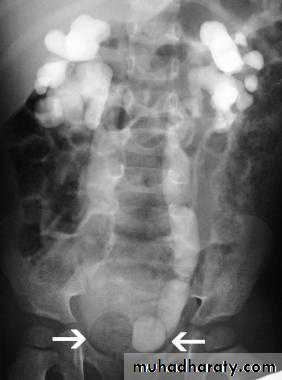

Calcification of the urinary bladder wall

bladder exstrophy

radiographic appearance in bladder exstrophy. It describes wide midline separation of the pubic bones.Bladder exstrophy (also known as ectopia vesicae) refers to a herniation of the urinary bladder through an anterior abdominal wall defect. The severity of these defects is widely variable.